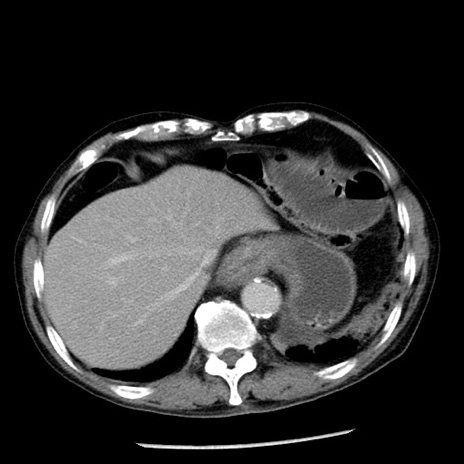

症例26(横断像)

【症例】80歳代男性

【主訴】嘔吐

【現病歴】昨晩2回嘔吐あり、今朝になっても嘔吐あり。来院。

【既往歴】胃潰瘍

【身体所見】意識清明、BT 37.6℃、BP 166/95mmHg、HR 100bpm、SpO2 97%、腹部:平坦・軟、腸蠕動音聴取良好、圧痛なし。

【データ】WBC 21900、CRP 1.46